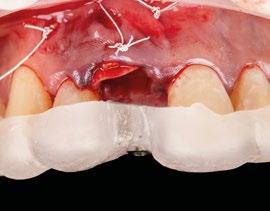

1.- Quitamos la corona ferulizada. (Figura 15)

2.- Extraemos de manera meticulosa la raíz del diente afectado. (Figura 16)

3.- Legramos toda la zona del lecho implantario con el fin de poder eliminar cualquier resto de tejido de granulación.

4.- Desepitelizamos en margen gingival. (Figura 17)

5.- Tunelizamos el defecto vestibular para alojar el injerto de tejido conectivo. (Figura 18)

6.- Colocamos injerto de tejido conectivo. (Figura 19)

7.- Interponemos membrana reabsorbible entre tejido conectivo y alveolo. (Figuras 20 y 21)

8.- Realizamos osteotomía mediante férula quirúrgica utilizando fresa piloto. (Figuras 22 a 24)